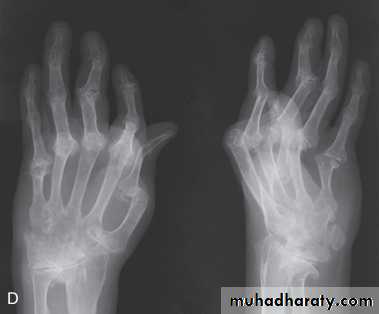

Symmetrical polyarthritis occurs in about 25% of cases.It predominates in women and may strongly resemble RA, with symmetrical involvement of small and large joints in both upper and lower limbs.

Nodules and other extraarticular features of RA are absent and arthritis is generally less extensive and more benign.

Much of the hand deformity often results from tenosynovitis and soft tissue contractures.

Xrays may be normal or show erosive change with joint space narrowing. Features that favour PsA over RA include the characteristic distribution of proliferative erosions with marked new bone formation, absence of periarticular osteoporosis and osteosclerosis.